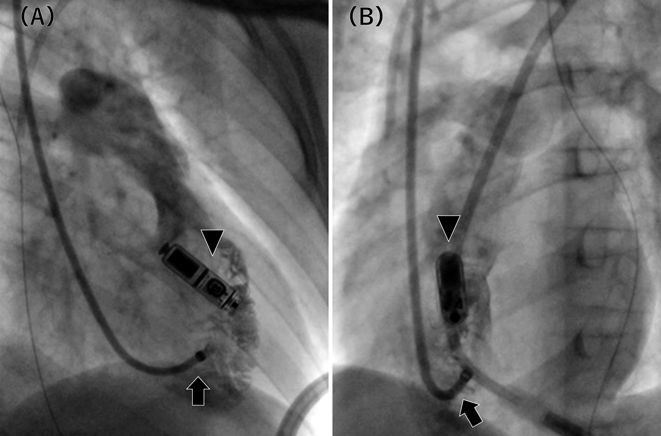

Fig. 5 Fluoroscopic images in right anterior oblique view (A) and left anterior oblique view (B)

The right ventricle was contrasted through the long sheath (arrow). The tip of the long sheath was sufficiently distant from the LPM (triangle). The biopsy forceps could enter the right ventricle through the long sheath, allowing myocardial biopsy from the right ventricular septum without interfering with the LPM.